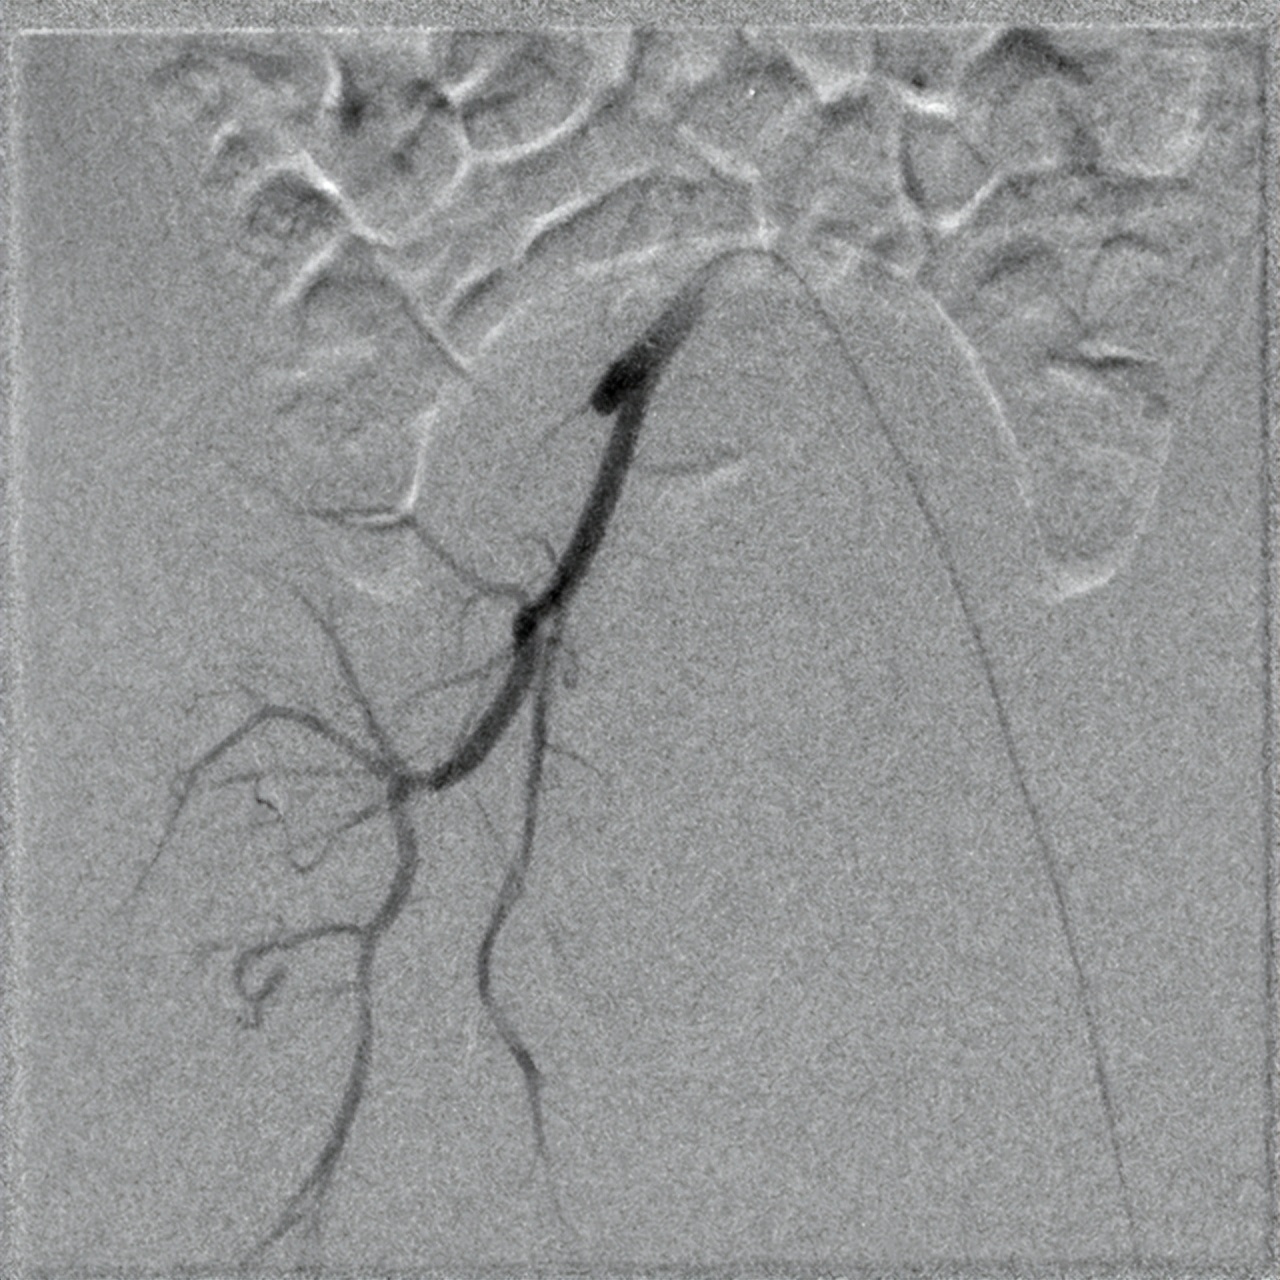

我看到患儿后,告诉家长不用担心,动脉血栓我们团队也是可以治好的。随后急诊,在介入手术室,全麻下给孩子做了动脉造影,明确血管狭窄情况,及血栓形成情况。继而,在导丝、导管的引导下,行动脉溶栓,球囊扩张。治疗后,血管立刻开通。家人十分感激,表示一定要感谢我们介入血管瘤科为孩子保住了双腿。

术前造影右下肢髂动脉动脉闭塞、血栓形成

术后右下肢股动脉通畅